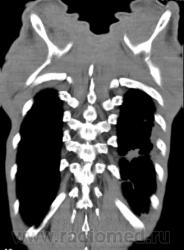

В этом году пациент взят на "контроль"

Прямая и "семерка".

6 и 9 срезы.